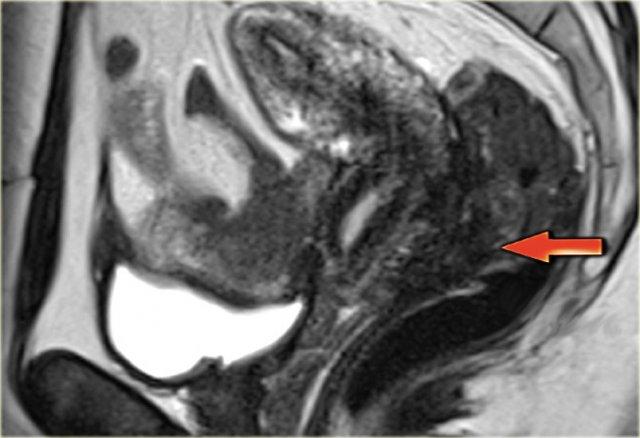

Hình ảnh chuỗi xung T2W mặt phẳng đứng dọc minh họa lạc nội mạc tử cung xâm lấn trực tràng và lạc nội mạc tử cung xâm lấn bàng quang

Hình ảnh T2W mặt phẳng đứng dọc này cho thấy lạc nội mạc tử cung xâm lấn sâu tại túi cùng sau với xâm lấn thành trực tràng.

Hình ảnh T2W của lạc nội mạc tử cung xâm lấn torus uterinus.

Hình ảnh T2W cho thấy lạc nội mạc tử cung xâm lấn sâu tại vòm âm đạo sau và torus uterinus.

Không có xâm lấn thành ruột.

Hình ảnh chuỗi xung T2W minh họa sự xâm lấn dây chằng tử cung-cùng bên trái.